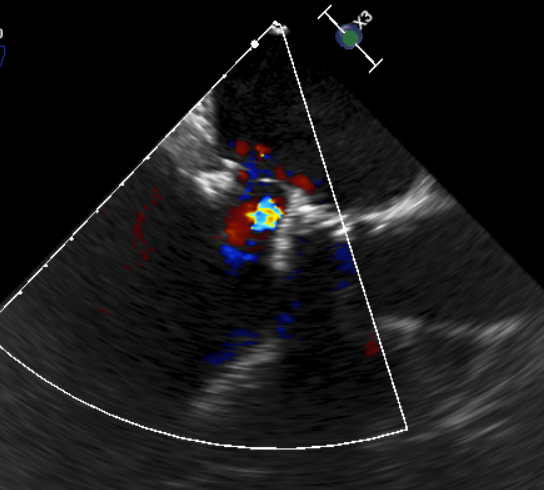

原生物瓣少量反流

过瓣流增快,呈“五彩状”

CDFI提示过瓣血流通畅

CDFI示少量瓣周漏